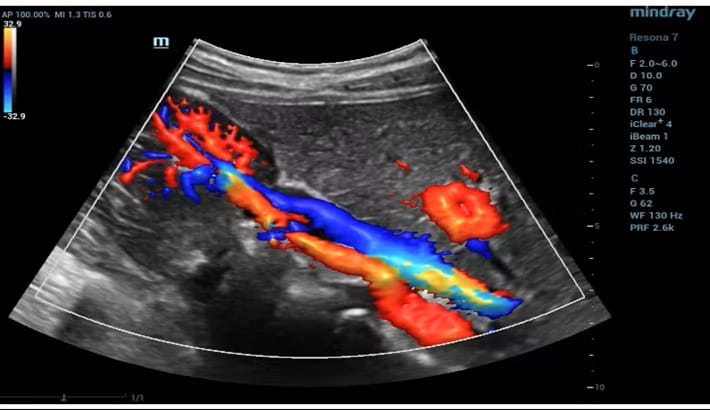

سونوگرافی داپلر رنگی یکی از پیشرفتهترین روشهای تصویربرداری است که علاوه بر نمایش ساختار اندامها، جریان خون در عروق را نیز بررسی میکند. بسیاری از بیماران هنگام جستجو برای بهترین مرکز سونوگرافی شیراز با نام داپلر رنگی مواجه میشوند؛ اما دقیقاً نمیدانند این روش چه تفاوتی با سونوگرافی معمولی دارد.

در این تکنیک، امواج صوتی پس از برخورد با گلبولهای قرمز در حال حرکت؛ بازتاب پیدا میکنند؛ سپس دستگاه این تغییرات را به تصویر رنگی تبدیل میکند. نتیجه این فرایند، مشاهده جهت و سرعت جریان خون بهصورت واضح است. به همین دلیل مراجعه به بهترین مرکز سونوگرافی شیراز برای انجام داپلر اهمیت زیادی دارد؛ زیرا کیفیت دستگاه و مهارت پزشک مستقیماً بر دقت نتیجه اثر میگذارد.

سونوگرافی داپلر رنگی در بررسی بسیاری از مشکلات عروقی کاربرد دارد. پزشکان معمولاً زمانی بیمار را به بهترین مرکز سونوگرافی شیراز ارجاع میدهند که نیاز به ارزیابی دقیق جریان خون وجود داشته باشد.

از جمله کاربردهای رایج میتوان به بررسی عروق پا برای تشخیص لخته خون، ارزیابی عروق گردن و کنترل وضعیت جنین در بارداری اشاره کرد. دقت این روش باعث شده داپلر به یکی از ابزارهای مهم تشخیصی تبدیل شود.